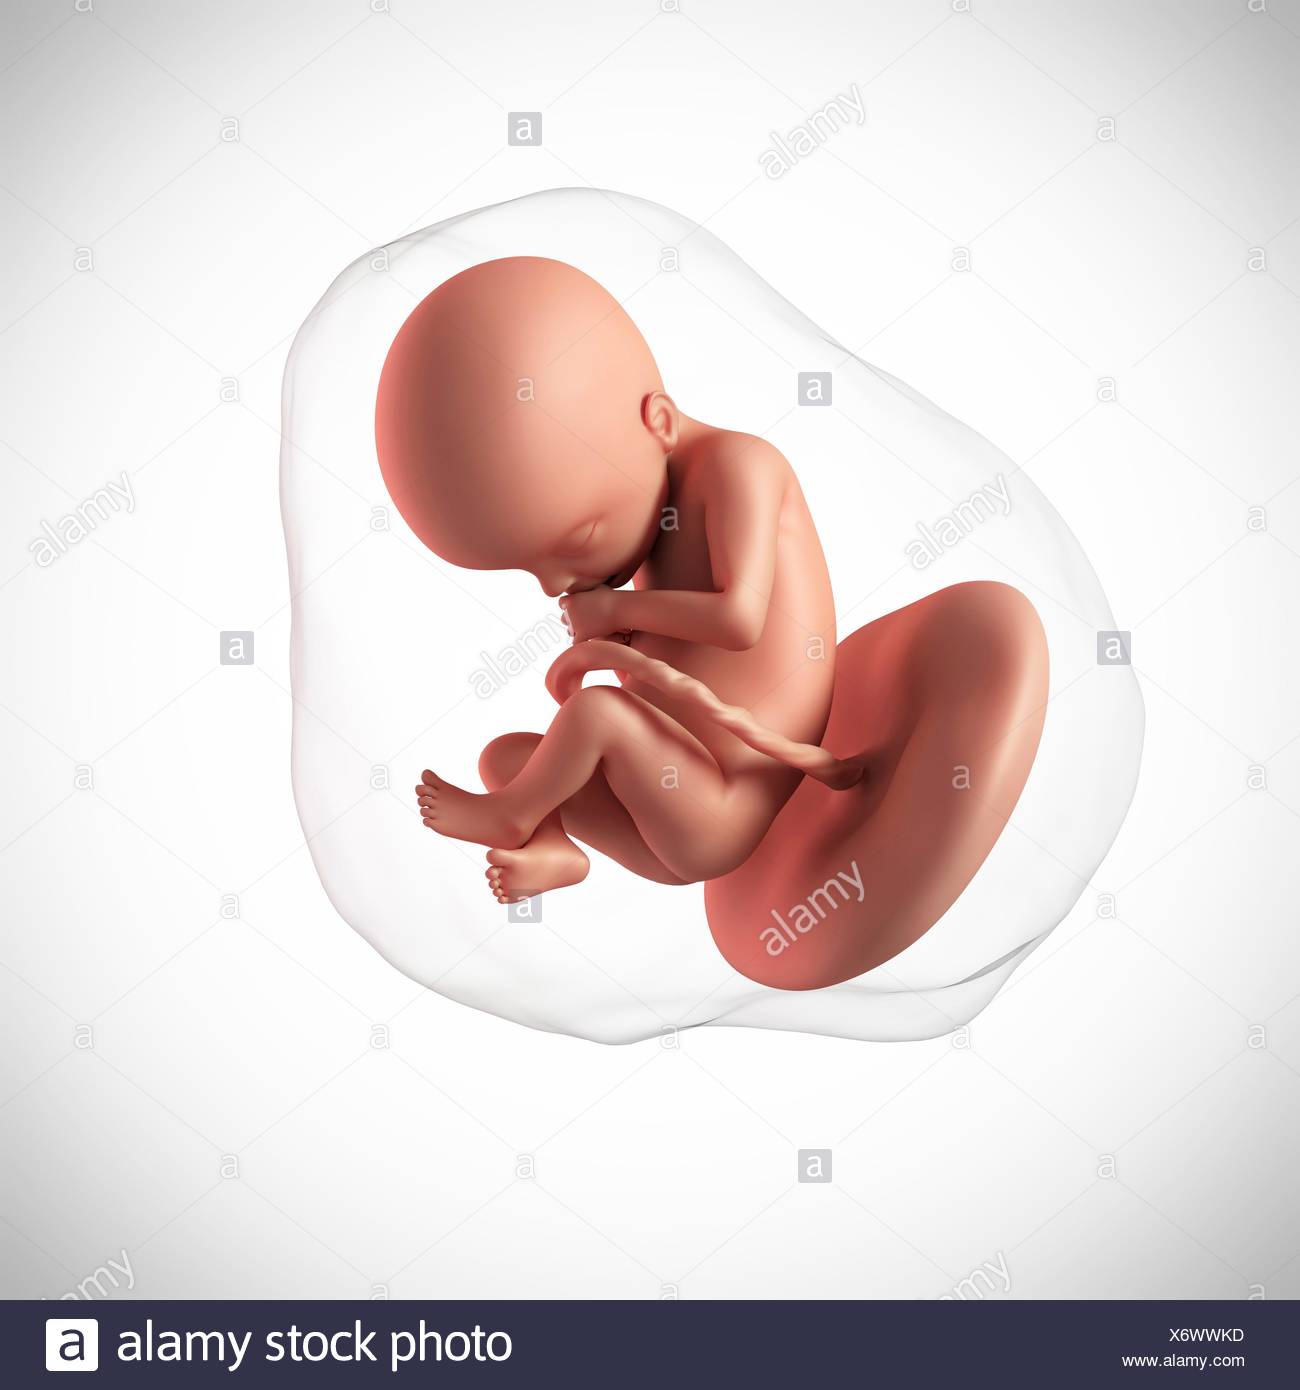

Una Settimana 22 Del Feto Illustrazione Di Stock Illustrazione Di Biologia 101127188

Settimana Feto Umano 22 Settimana Reso Feto 22 Accurato Illustrazione Medically Umano 3d Canstock

Eta Feto Umano 22 Settimane 3d Fondo Bianco Stock Photo 160556350